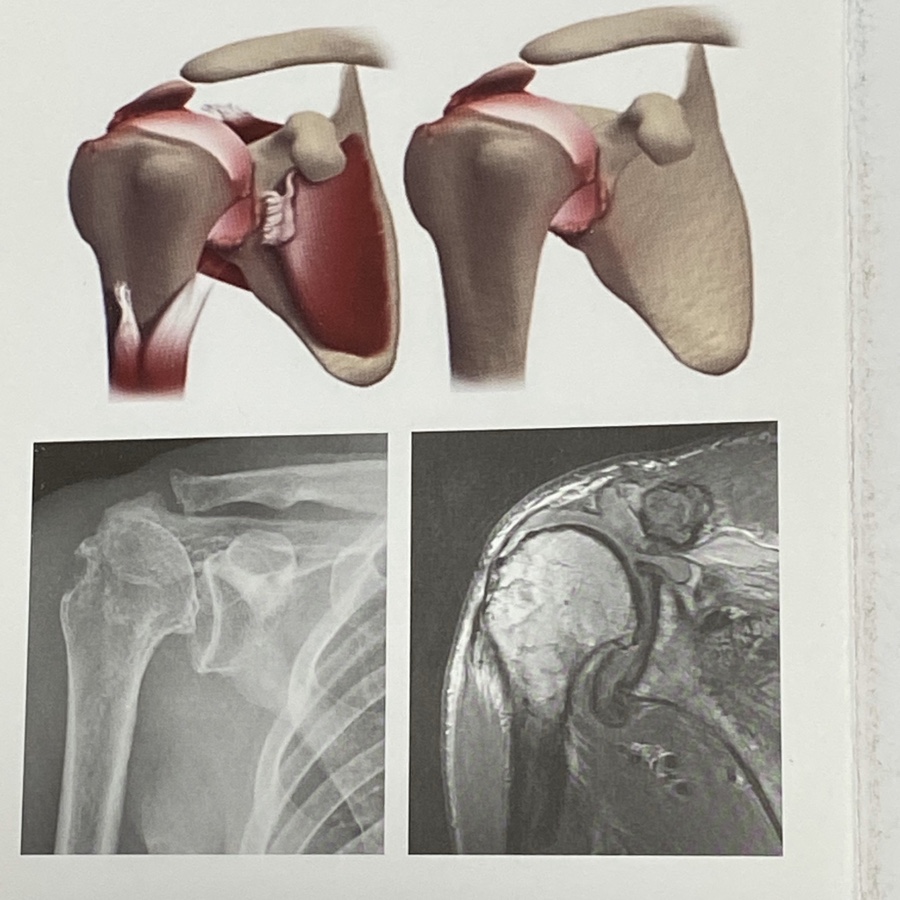

4.회전근개 파열 관절병증

파열이 심한 상태로 치료가 안될 경우 관절면의

손상을 가져오게 됩니다.

일반적 골관절염과 달리 퇴행성 골관절염에 추가되어

회전근개가 모두 파열되어 없는 상태이기 때문에

상완골이 윗쪽으로 전이되고 능동적으로 팔을

들 수 없는 상황이 발생 하기도 합니다